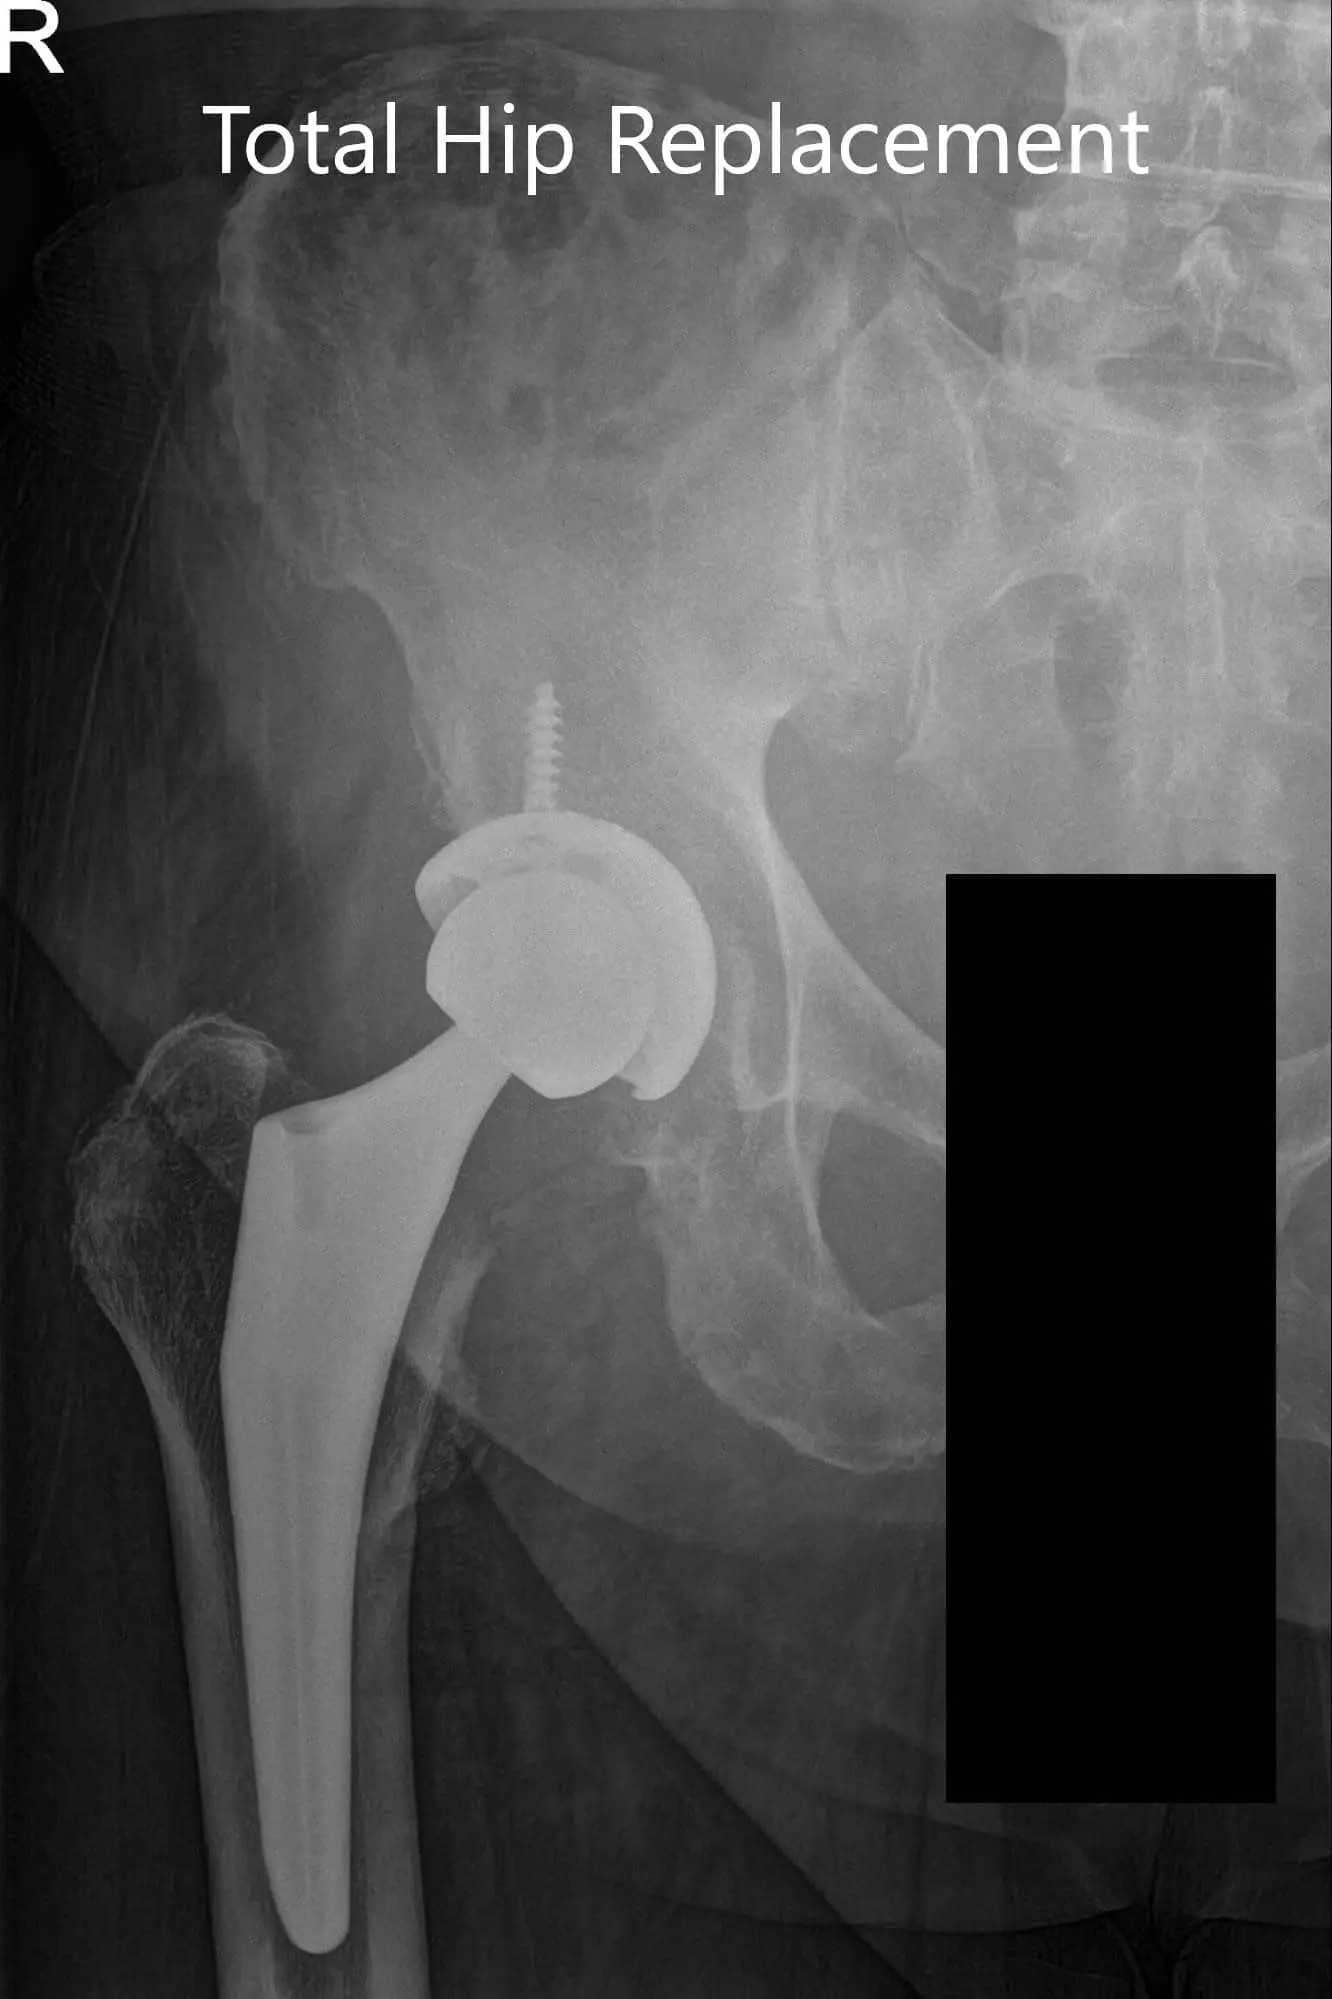

Postoperative X-ray showing AP and frog-leg lateral views of the right hip

Postoperative X-ray showing AP and frog-leg lateral views of the right hip - img 2

IMPLANTS USED: 52 mm cup with 6.5 mm screw, 25 mm in length with a 0-degree polyethylene with a 127-degree neck stem with a ceramic femoral head 36 mm minus 2.5.